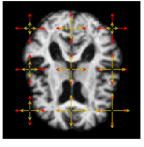

Refer to caption

Figure 4: From left: (1.) Pixel-wise variation in the data. (2.) Variation estimated by the model. (3.) Estimates of the variance parameter τk2superscriptsubscript𝜏𝑘2\tau_{k}^{2} compaired to the true values (4.) Estimates of the variance and amplitude parameter compaired to the true values. The length of the arrows correspond to τkλksubscript𝜏𝑘subscript𝜆𝑘\tau_{k}\lambda_{k}. The arrows show the location and width of the noise fields. The red arrows correspond to the true values, while the yellow defines the resulting estimated parameters.

Fig. 4 shows the initial brain, I0subscript𝐼0I_{0}, with a comparison of the true values of τksubscript𝜏𝑘\tau_{k} and λksubscript𝜆𝑘\lambda_{k}, and the values found by the optimisation procedure. The red arrows are the true values, and the yellow defines the estimated parameter values. The model is able to retrieve the parameters of τksubscript𝜏𝑘\tau_{k} for all k=1,,9𝑘19k=1,\ldots,9. It also returns a good estimate of the amplitude parameters, in particular for the noise fields located inside the brain. For noise fields on the boundary of the brain or in the background, the model does not have access to enough information in the intensity differences to return precise estimates of the amplitude parameters.